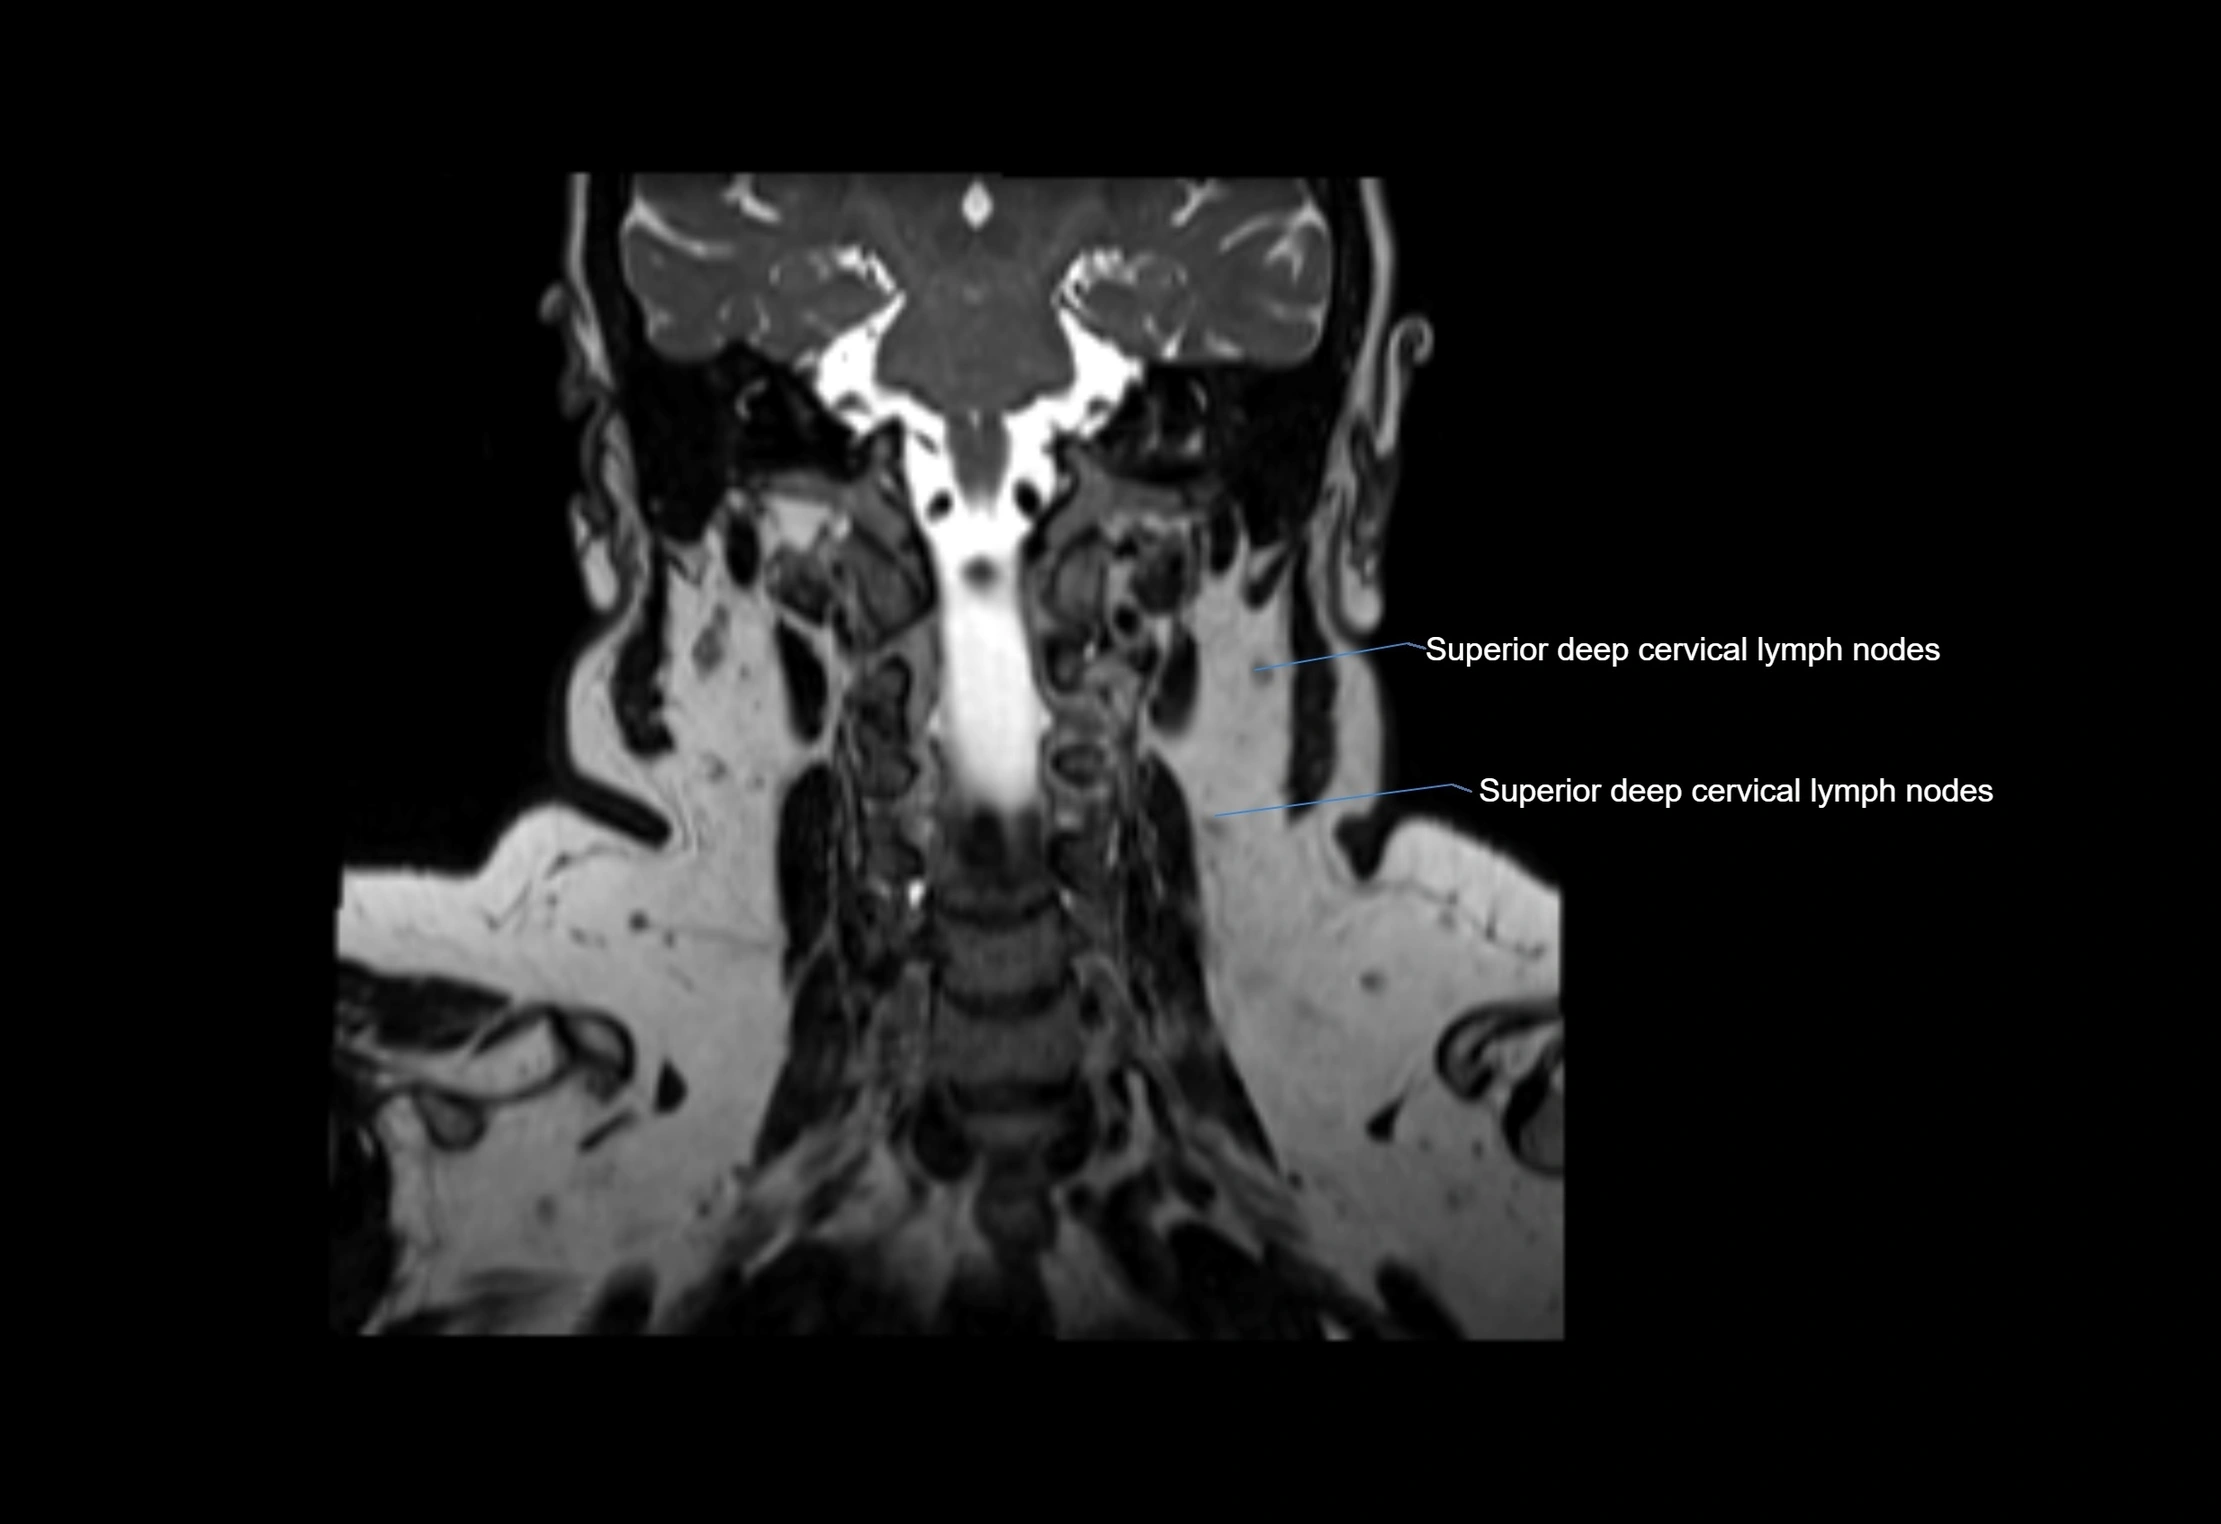

Location

• Found along primary lymph node chains, including preauricular, submandibular, parotid, and occipital regions

• Embedded in subcutaneous fat or superficial fascia, often lateral or posterior to primary nodes

• Variable in number; may occur unilaterally or bilaterally, depending on individual anatomy

MRI images